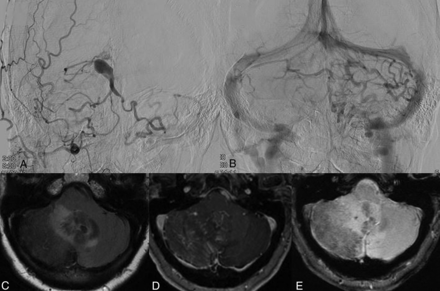

Pseudophlebitic pattern in a patient with a tentorial dural arteriovenous fistula presenting with ataxia. A, Right external carotid artery angiogram shows a tentorial dural arteriovenous fistula with reflux into the bilateral cerebellar hemispheres. B, Parenchymal venous phase of a left vertebral artery injection shows a pseudophlebitic pattern of the cerebellar parenchymal veins. C, FLAIR MR imaging shows edema in the bilateral cerebellar hemispheres and vermis. D, Postcontrast MR imaging shows dilated transmedullary veins in the right cerebellar hemisphere and vermis. E, Gradient recalled-echo MR imaging shows chronic hemosiderin deposition in the right cerebellar hemisphere.